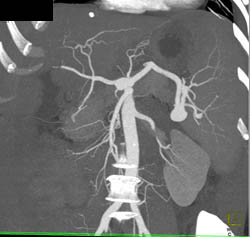

Pseudoaneurysm Left Groin Off SFA